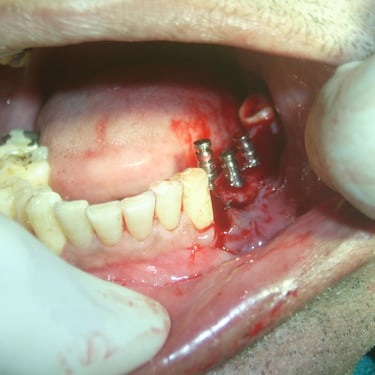

Implant Dentistry/Dental Implants

Implant planning using CBCT Single/Multiple teeth implants All on 4 and All on 6 Sinus lift: direct & indirect Ridge split using Piezo surgery Bone Grafting Soft tissue grafting A-PRF, I-PRF